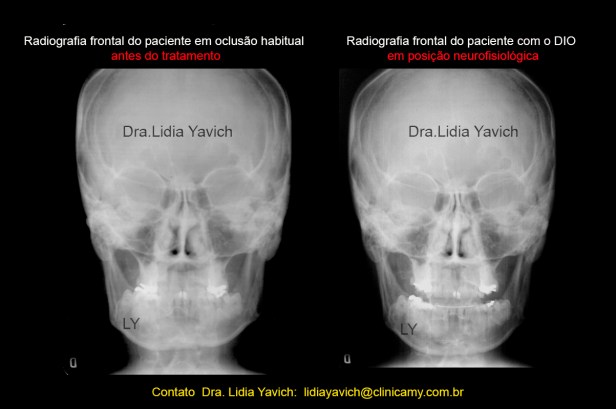

Comparação das radiografias frontais a primeira em oclusão habitual e a segunda com o dispositivo intraoral em posição neuromuscular fisiológica.

Melhora do alinhamento tridimensional da mandíbula, nos não podemos consertar as diferenças estruturais dos côndilos mandibulares, mas sim podemos equilibrar os músculos.

Comparação das radiografias frontais: traçado de cor na mandíbula para realçar o alinhamento tridimensional da mandíbula em posição neuromuscular fisiológica.